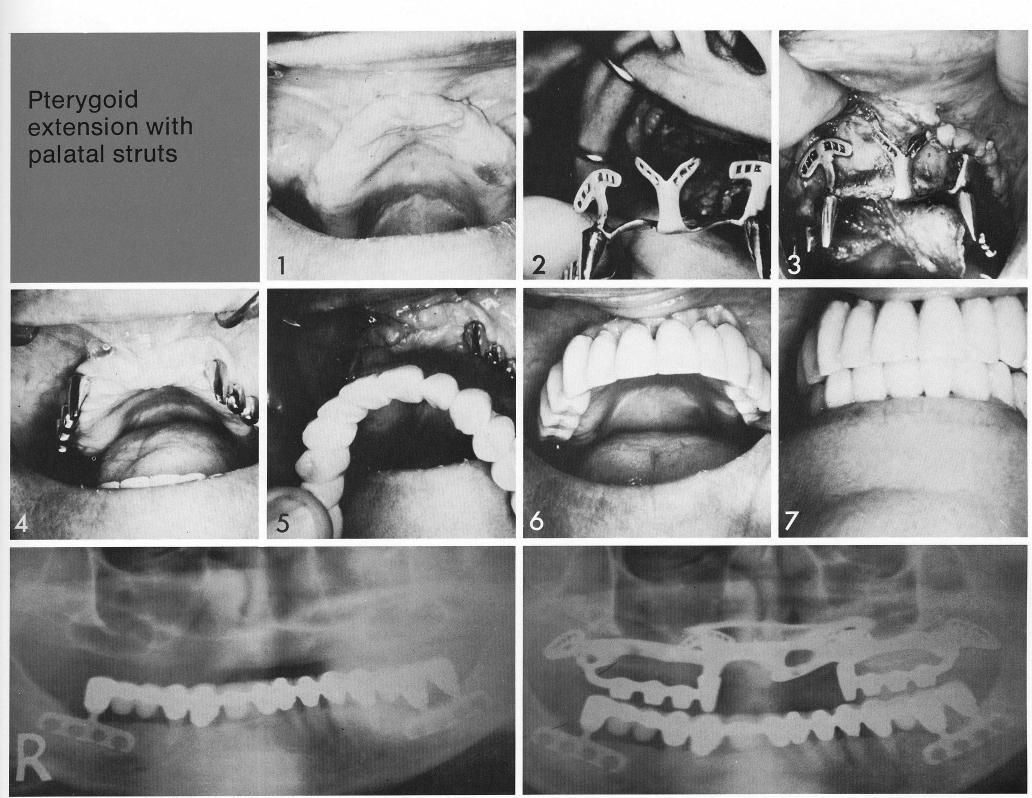

Pterygoid extension with palatal struts

The anterior labial portion of this pterygoid extension implant is somewhat unusual. For a really secure fit for the totally edentulous patient (1), the anterior nasal spine is used for an additional cross strut and for more support (2,3). Note that the wings of each cross strut are fenestrated to lighten the implant and permit close readaptation of the soft tissues to bone, as evidenced by the uncomplicated healing (4). The finished restoration (5) is far lighter in weight and more secure than the patient's old denture.

1 Unusual anterior portion of maxillary pterygoid extension implant